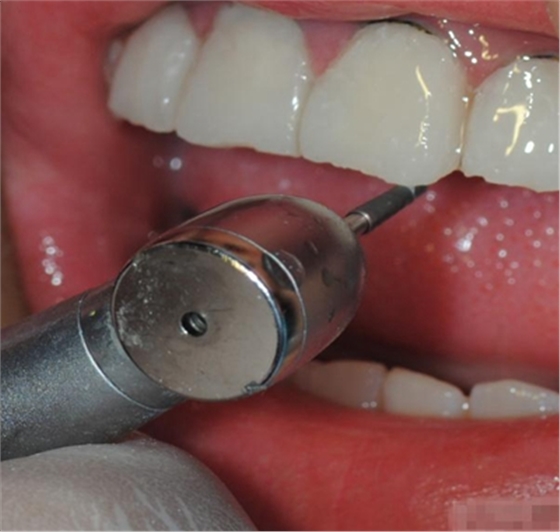

【比色】清潔牙面

比色

談到比色 要考慮天然牙:亮度 、飽和度、色相 、透明度、半透明度 ····